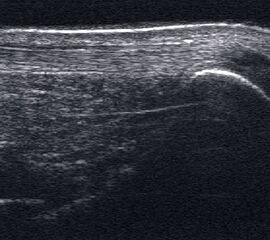

Achillessehne

Achillessehnenrupturen

Lagerung: Bauchlage, ggf. Sprunggelenk mittels Rolle unterlagert.

Schnittführung: LS über der Achillessehne, ggf. in leichter manueller Vorspannung der Achillessehne, damit diese parallel zum Schallkopf optimal eingestelt werden kann (Abb. 52).

Referenzstruktur: Direkt unter der Haut und der dünnen Subkutis liegt echogen und straff parallel die Achillessehne mit ihrem echogenen Peritendineum (Abb. 53), Tuber calcanei.

Befunde: Da die Sehne zumeist nicht glatt, sondern bündelförmig reißt, stellen sich auch in der Sonographie anders als bei den Peroneal- und Flexorensehnen keine spargelspitzenähnlichen Rissenden dar. Echogene Rissränder, umgeben von echoarmem Hämatom sind beweisend für eine Ruptur. Risse der Achillessehne können auch nur einen Teil des Sehnenquerschnitts betreffen. Daher ist die Untersuchung verschiedener TS bedeutsam (Abb. 54 bis 56). Unter Kontrolle am Monitor kann die Diagnose in maximaler Dorsalextension klarer gestellt werden (Abb. 57).

In maximaler Plantarflexion kann versucht werden, die Sehnenstümpfe anzunähern. Für die Therapieplanung ist entscheidend, ob sich die Stümpfe der Sehne in 30° Plantarflexion in Kontakt bringen lassen. Dies ist beispielsweise Voraussetzung für eine konservative Behandlung.